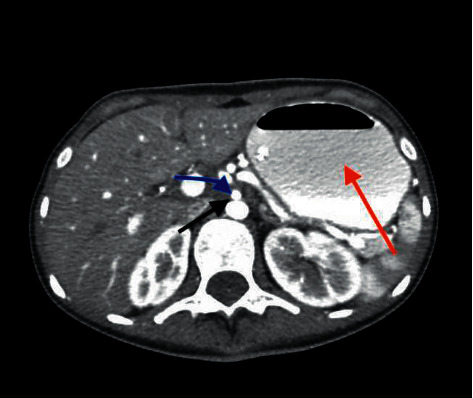

Superior mesenteric artery (SMA) syndrome is a rare etiology of upper gastrointestinal obstruction. The measured angle between the SMA and the aorta is typically between 38 and 65° and maintained by mesenteric fat. Excessive fat loss can lead to intestinal obstruction due to an exaggerated acute angularity of the SMA, compressing the third part of the duodenum. We present a 22-year-old female with a history of aplastic anemia, status post bone-marrow transplant, who presented with intractable nausea and had confirmed SMA syndrome on CT angiography. Subsequently, the patient underwent nasogastric decompression and successful laparoscopic duodenojejunostomy.

摘要肠系膜上动脉症候群是一种罕见的上消化道梗阻病因。SMA与主动脉之间的测量角度通常在38°至65°之间,由肠系膜脂肪维持。由于SMA的急性角度过大,压迫十二指肠的第三部分,脂肪的过度减少可导致肠梗阻。我们报告一位22岁的女性,有再生障碍性贫血史,骨髓移植后的状态,她表现为顽固性恶心,CT血管造影证实为SMA综合征。随后,患者接受了鼻胃减压术和成功的腹腔镜十二指肠空肠吻合术。